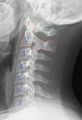

颈椎病、椎间盘狭窄和骨质增生等病症会导致颈椎退行性改变。通过X光检查可以发现这些病变,并能对疾病的状态进行一个0-4级的分期。包括颈椎无病变(0期)、早期的少量骨质增生(1期),轻度的明确的骨质增生(2期),中度骨质增生并伴有椎间盘间隙狭窄或缩窄(3期),重度骨质增生,椎间盘间隙严重缩窄,以及严重的椎骨终板硬化(4)。[2][3][4]

• 颈椎X光图像